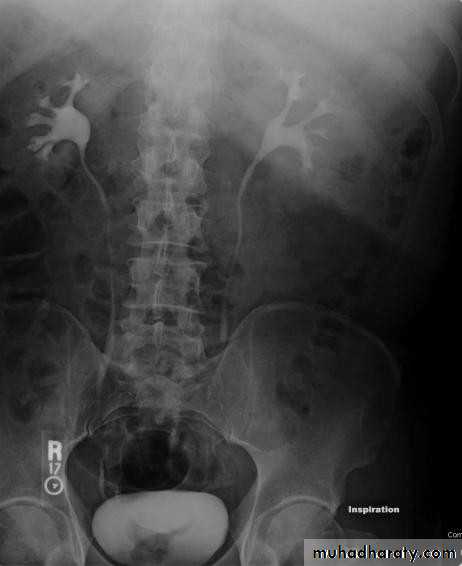

Urography:

Indications:When detailed demonstration of the pelvicaliceal system and ureters are required

Suspected ureteric injury, e.g. following pelvic surgery or trauma

Assessment of acute ureteric colic

• Intravenous (Excretory) Urography

• Check the Kidneys: outline, size, site

• Check the calyces: cupped• Check renal pelvis and ureter

• Check the bladder